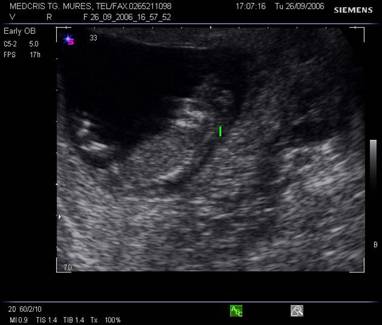

Fig. nr.109 Aspecte morfologice ale sarcinii normale la 12 saptamani( Schematic )

Fig. nr.110 Aspecte morfologice ale sarcinii la inceputul trimestrului II ( schematic )